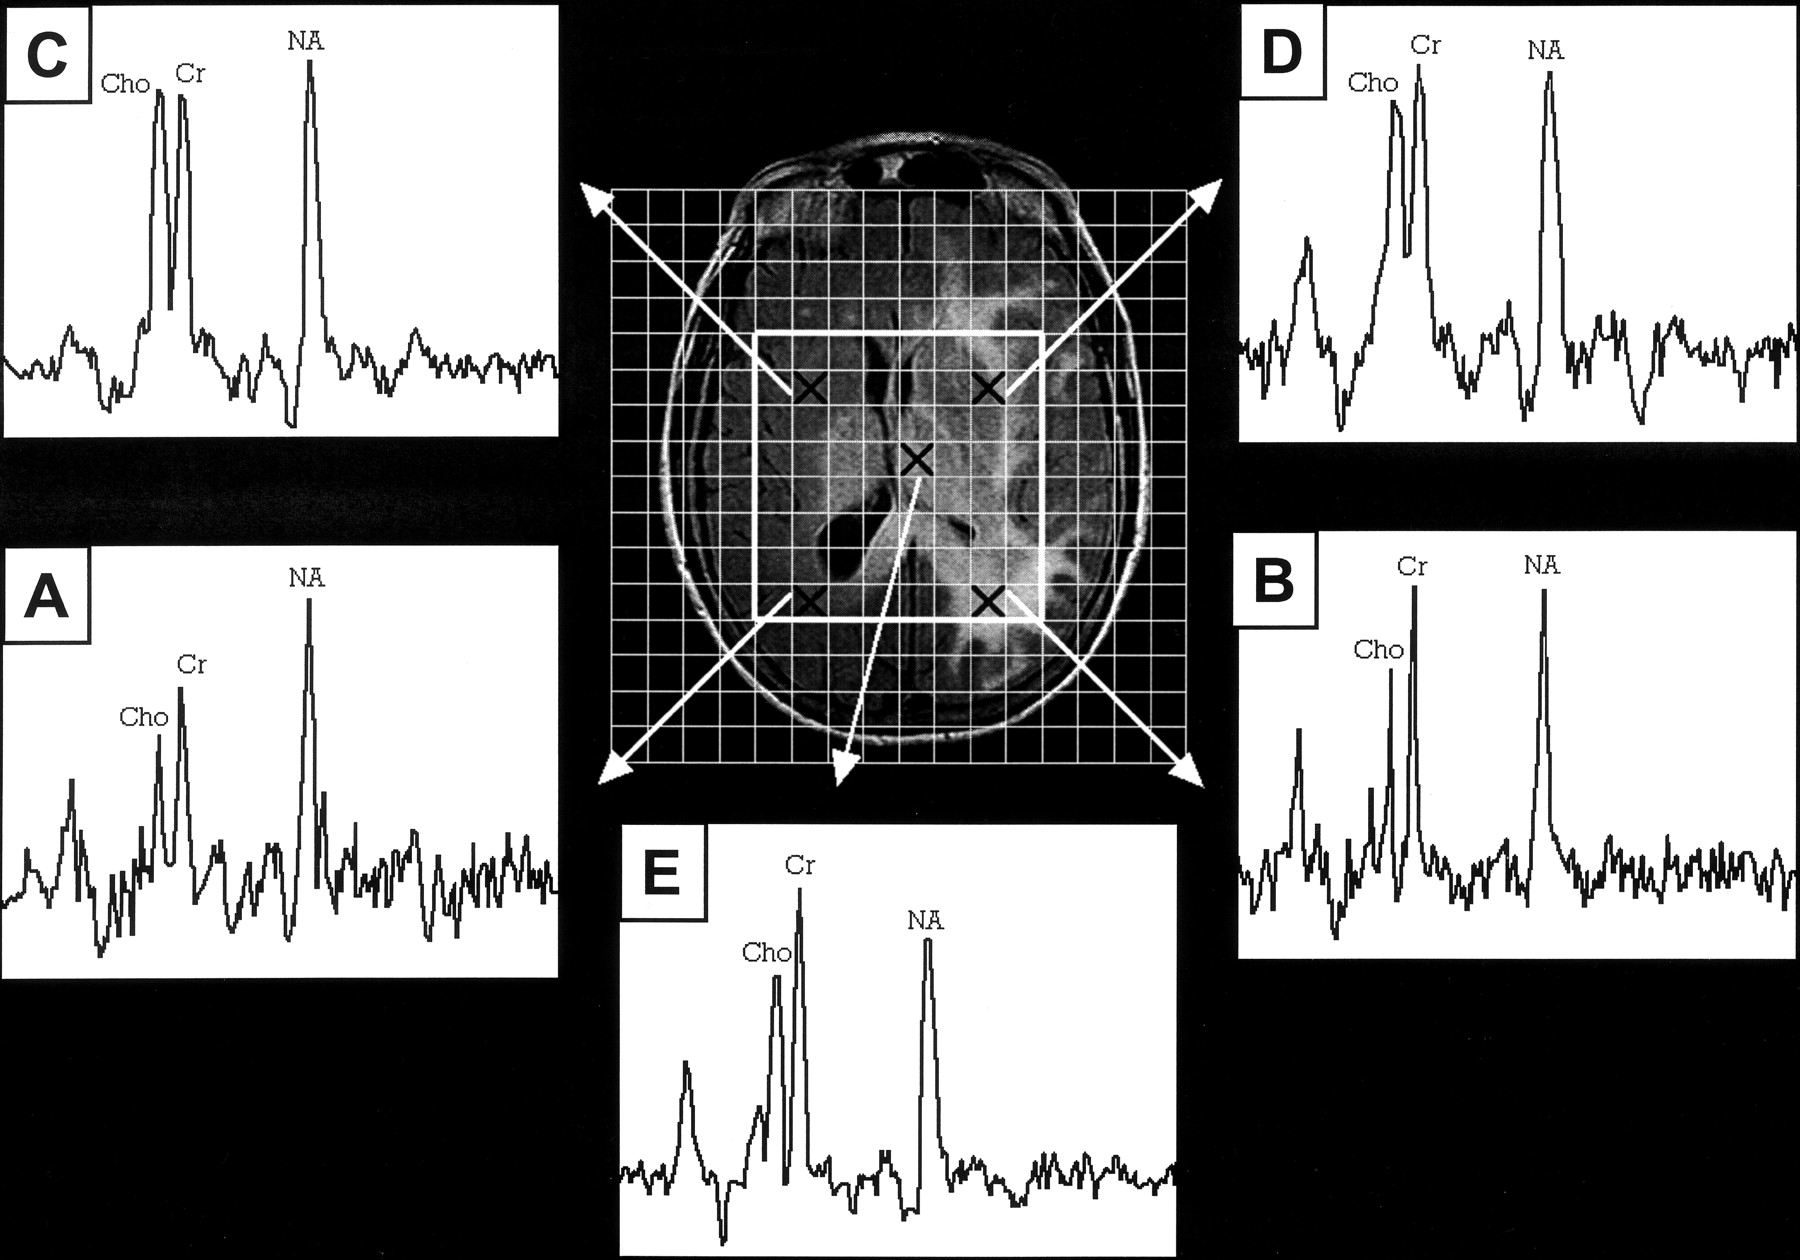

2D MR spectroscopic imaging was subsequently performed. The 2D section was co-registered with the FLAIR image shown in Figures 1 and 2. Multi-voxel (16 × 16 array, 18 × 18 cm2 region of interest), water-suppressed spectra were acquired before the IV administration of contrast medium by using a PRESS sequence (1500/135, two accumulations, bandwidth ± 1000 Hz, and 2048 data points) with spatial saturation of the outer volume, sparing the central 8 × 8 array (Fig 3). Each (sub)voxel of the array was approximately 2.5 mL (1.125 × 1.125 × 2 cm3). The spectra (Fig 3) were generated by using a multi-voxel spectral analysis routine analogous to the one used for single voxel data (6).

Spectroscopic imaging. Multi-voxel spectra (TE 135) from five different locations (marked by Xs) indicated on the axial FLAIR localizer. A, Right periatrial region. B, Left periatrial region. C, Right basal ganglia region. D, Left basal ganglia region. E, Left thalamus.

The MR spectroscopic imaging results allowed qualitative comparisons between right and left periatrial PRESS spectra (Fig 3, A and B, respectively) and comparisons with spectra from other locations in the 2D MR spectroscopic imaging grid: basal ganglia spectra (Fig 3, C and D) and the spectrum from the left thalamus (Fig 3, E). For the periatrial spectra (Fig 3, A and B), the relative peak amplitudes of NA, Cho, and Cr were similar to those shown by the corresponding single voxel spectra (Fig 2, A2 and B2, respectively). The left thalamic spectrum (Fig 3, E) was similar in appearance to the left periatrial and basal ganglia spectra (Fig 3, B and D), showing no elevation of Cho relative to Cr at these diverse locations within the region of abnormal FLAIR signal intensity. LCModel analysis of the left thalamic spectrum yielded NA/Cr = 0.78, Cho/Cr = 0.25, and Cho/NA = 0.31.